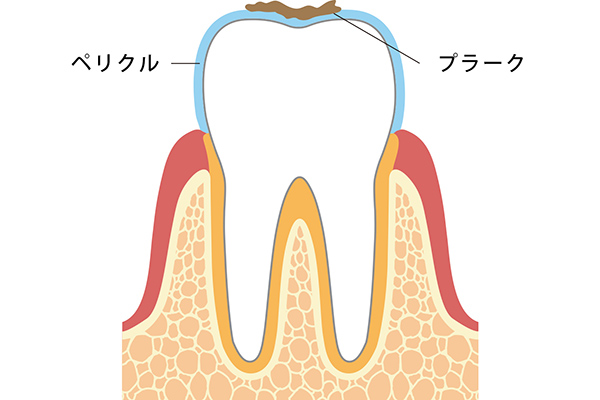

むし歯になる原因や流れを説明していきます。唾液中の糖タンパク質を主成分とした歯牙表面に形成される、薄い被膜のことを「ペリクル」といいます。このペリクルが足がかりとなり、歯の表面に細菌が溜まります。そして、この集合体を「歯垢(プラーク)」といいます。この歯垢(プラーク)が産生する酸により、歯が溶けると「むし歯」になります。歯垢(プラーク)の見た目は白色、黄白色であり、ネバネバとした粘着性の性状をしています。そのため、うがいだけで洗い流す事は難しく、ブラッシングにより取り除く事ができます。